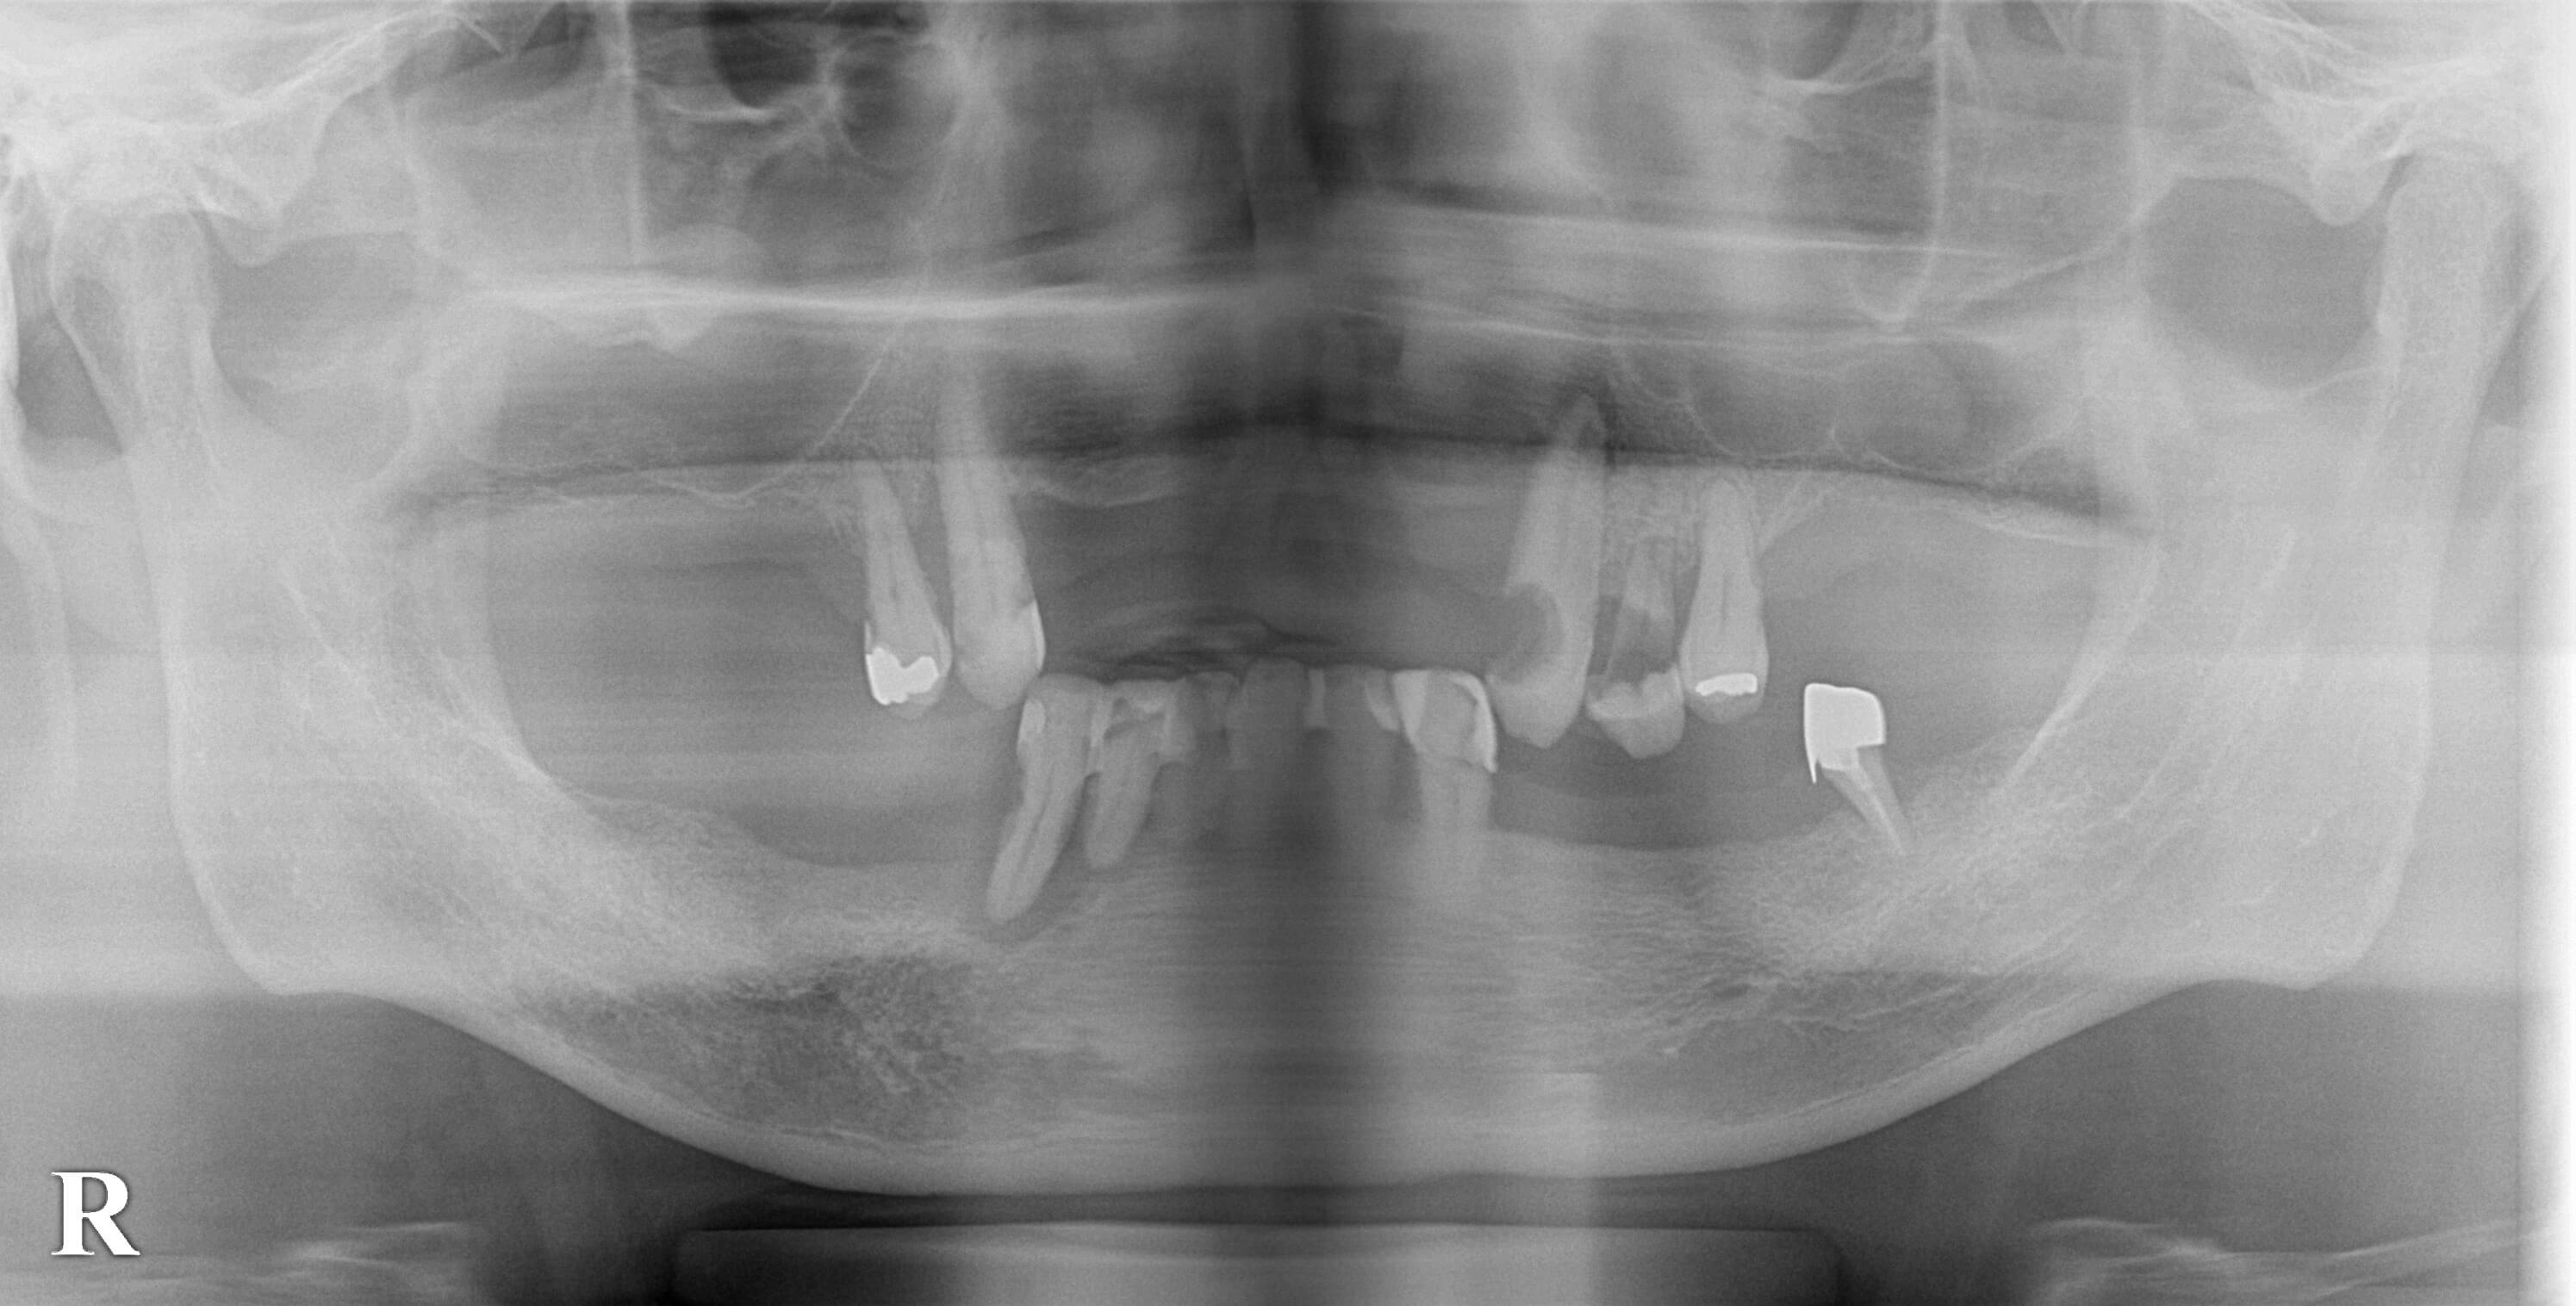

上下とも、ボロボロの歯ばかりになってしまっているのですが、これで何とか食事をされていたそうです。

こうなると、上下とも1本か2本残して、あるいはすべて抜歯して、固定式の歯をインプラントで回復するのが最良かと思います。

そこで、上顎に4本、下顎に2本のインプラントを埋入し、入れ歯の維持装置を装着して、

安定した義歯を作製するという治療計画を提案しました。

それで了承されましたので、本日、まずは下顎に2本のインプラント埋入術を施行しました。